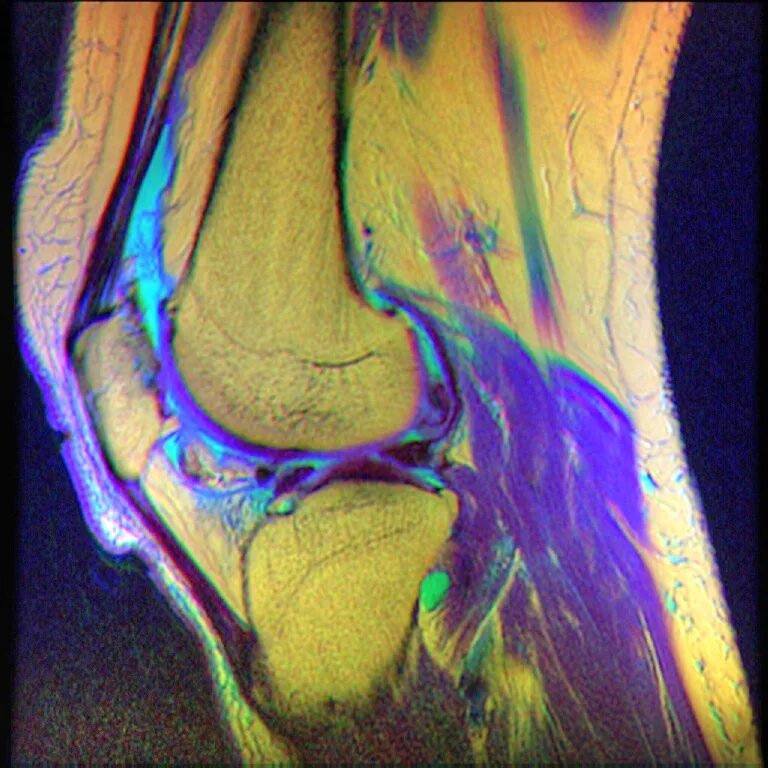

Повреждение хряща по outerbridge